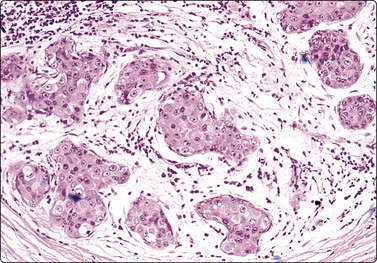

image image

Fig. 7.2 Non-neoplastic glandular breast tissue and low-grade duct carcinoma

Low-power view; (A) Bimodal population of epithelial sheets and single bipolar nuclei of non-neoplastic glandular breast tissue; (B) Single population of epithelial cells in low-grade carcinoma (MGG, LP).

Fig. 7.3 Non-neoplastic glandular breast tissue and low-grade duct carcinoma

High-power view, air-dried smears; (A) Non-neoplastic glandular breast tissue; (B) Low-grade duct carcinoma. Note single bipolar nuclei in A, and absence of bipolar nuclei, relatively mild nuclear atypia and some loss of cohesion of malignant cells in B (MGG, HP).

Fig. 7.4 Non-neoplastic glandular breast tissue and low-grade duct carcinoma

High-power view, Pap-stained smears; (A) Bimodal population in smear from non-neoplastic breast; (B) Single and clustered cells in low-grade carcinoma; some single cells probably stromal (Pap, HP).